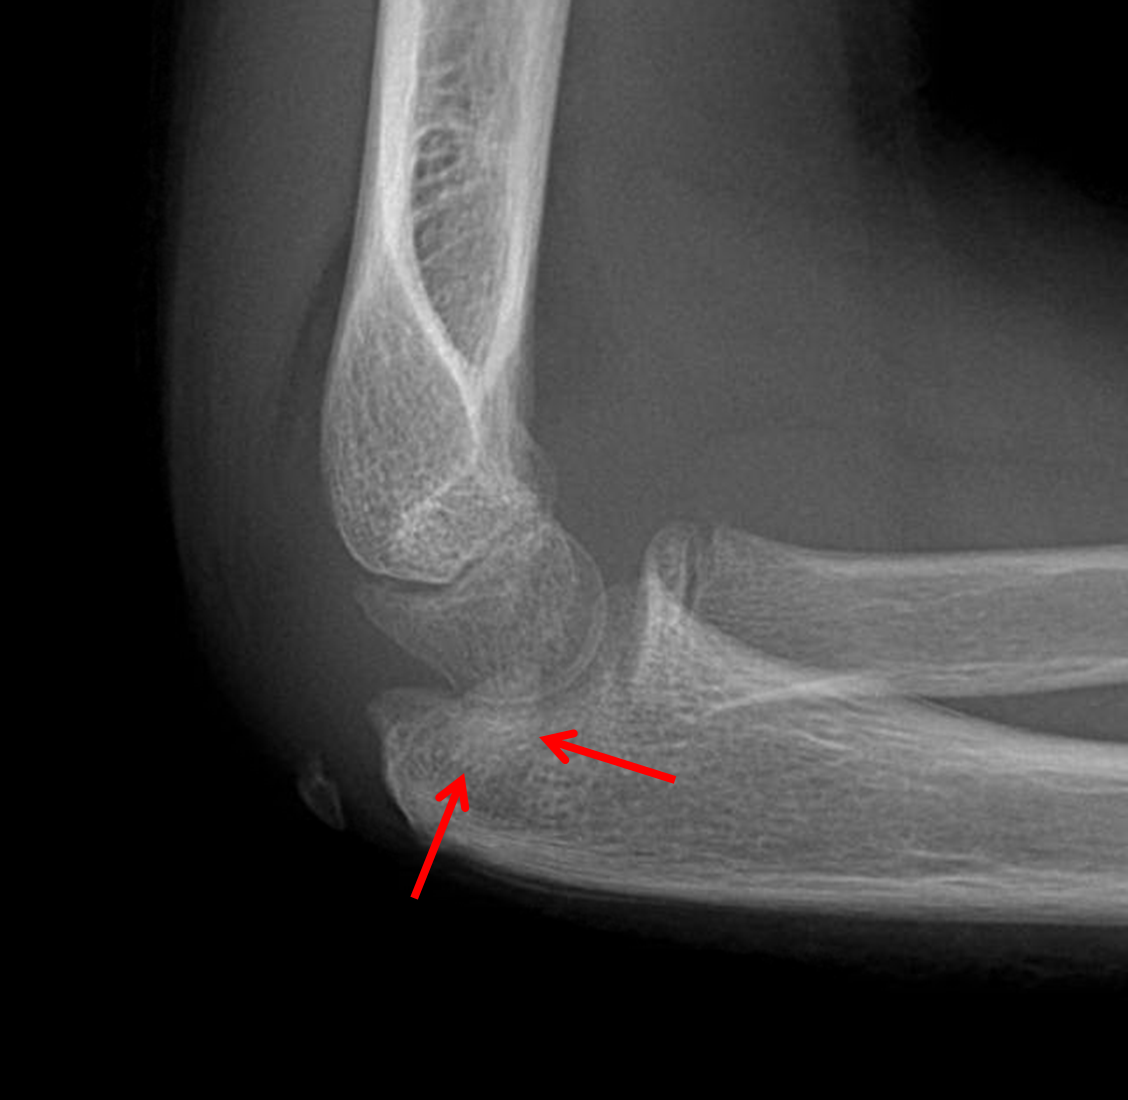

The elbow is the joint connecting the proper arm to the forearm. Recognizing an elbow joint effusion on lateral radiographs is an essential radiology skill.

While the fluid itself is not discretely seen because it is the same density as the surrounding muscles, an effusion can be an elbow joint effusion in the setting of trauma is typically a sign of an occult fracture. The approach to diagnosis depends on the joint involved. The articular surfaces of the bones are. Lateral and ap radiography usually reveals the. The term effusion can also be applied. While aspiration of the joint is considered the gold standard of treatment, this can be difficult for joints such as the hip. Joint effusion without visualized fracture on initial radiographs after trauma does not correlate with the presence of occult fracture in most cases (83%). Are you suffering from joint effusion & its getting really hard to tackle the pain? It may affect any joint. Commonly it involves the knee. The elbow is the joint connecting the proper arm to the forearm. Teaches you how to recognise an elbow joint effusion on lateral radiographs by identifying displaced elbow fat pads. Joint effusion is the abnormal accumulation of fluid caused by everything from an infection to arthritis. The elbow permits for the flexion and extension of the forearm, as well as rotation of the forearm and wrist. Learn how it is diagnosed and treated. Includes a description of the sail sign. Anterior fat pad sign indicates joint effusion/ injury when raised and becomes more perpendicular to the anterior humeral cortex (sail sign).